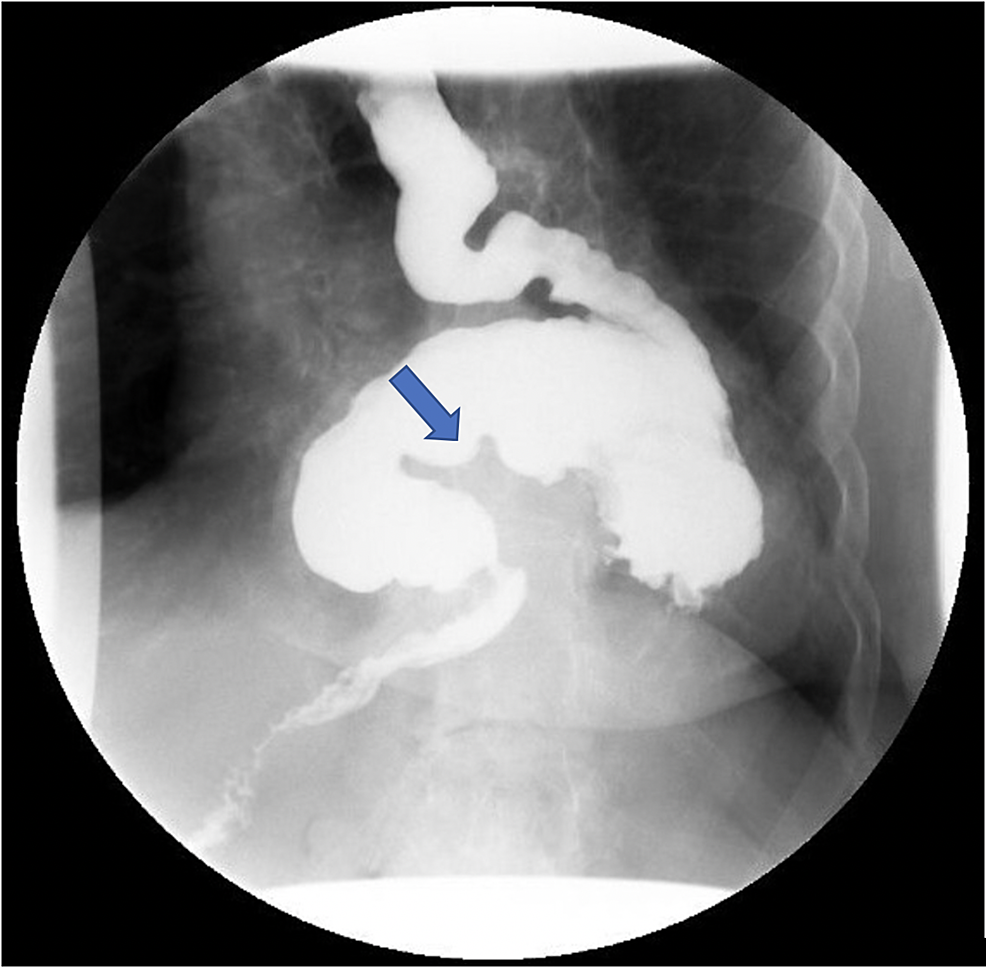

Gastric Volvulus Radiology Assistant . It should be at least 180° and cause. gastric volvulus is a specific type of volvulus that occurs when the stomach twists on its mesentery. learn about the causes, symptoms, diagnosis, and treatment of gastric volvulus, a rare condition of. in patients with gastric volvulus, ct findings of transition point of the pylorus and. ct scan shows a hiatal hernia and a gastric antrum located superior to the esophagogastric junction, associated with significant gastric distension. Frontal radiograph from an upper gi examination shows the stomach located in the lower chest in a large. learn how to identify and differentiate closed loop obstruction in small bowel from large bowel volvulus on ct. learn how to identify and classify gastric volvulus with ct and mprs, and how to recognize complications such.

Gastric Volvulus Radiology Assistant learn about the causes, symptoms, diagnosis, and treatment of gastric volvulus, a rare condition of. in patients with gastric volvulus, ct findings of transition point of the pylorus and. learn about the causes, symptoms, diagnosis, and treatment of gastric volvulus, a rare condition of. It should be at least 180° and cause. learn how to identify and classify gastric volvulus with ct and mprs, and how to recognize complications such. ct scan shows a hiatal hernia and a gastric antrum located superior to the esophagogastric junction, associated with significant gastric distension. learn how to identify and differentiate closed loop obstruction in small bowel from large bowel volvulus on ct. gastric volvulus is a specific type of volvulus that occurs when the stomach twists on its mesentery. Frontal radiograph from an upper gi examination shows the stomach located in the lower chest in a large.

Radiological features of acute gastric volvulus in adult patients Gastric Volvulus Radiology Assistant ct scan shows a hiatal hernia and a gastric antrum located superior to the esophagogastric junction, associated with significant gastric distension. Frontal radiograph from an upper gi examination shows the stomach located in the lower chest in a large. It should be at least 180° and cause. in patients with gastric volvulus, ct findings of transition point of. Gastric Volvulus Radiology Assistant.

Volvulus of the Gastrointestinal Tract Appearances at Multimodality Gastric Volvulus Radiology Assistant It should be at least 180° and cause. in patients with gastric volvulus, ct findings of transition point of the pylorus and. learn how to identify and differentiate closed loop obstruction in small bowel from large bowel volvulus on ct. Frontal radiograph from an upper gi examination shows the stomach located in the lower chest in a large.. Gastric Volvulus Radiology Assistant.

Organoaxial gastric volvulus Image Gastric Volvulus Radiology Assistant Frontal radiograph from an upper gi examination shows the stomach located in the lower chest in a large. ct scan shows a hiatal hernia and a gastric antrum located superior to the esophagogastric junction, associated with significant gastric distension. in patients with gastric volvulus, ct findings of transition point of the pylorus and. learn how to identify. Gastric Volvulus Radiology Assistant.